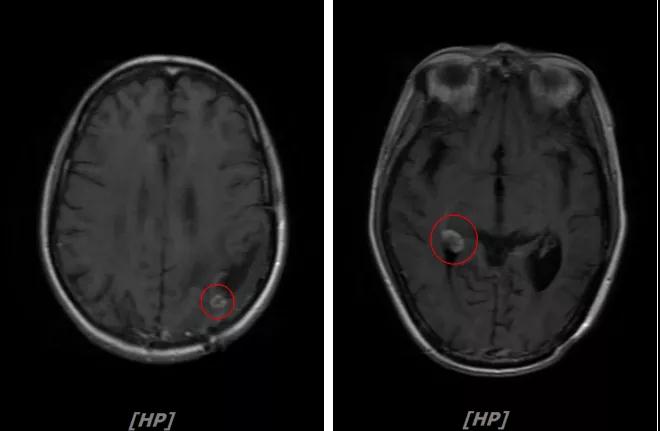

b.2014年3月全脑放疗结束后,予以LX方案治疗(拉帕替尼 1250mg qd+卡培他滨 1500mg bid)。每3个月规律复查,未见明显异常。下图为2014年6月患者行头颅增强MR检查,提示左顶叶脑转移瘤术后改变。

每3个月规律复查,未见明显异常。如2015年8月 头颅MR检查,提示:左顶叶脑转移瘤术后放疗后改变,对比前片2015年3月10日相仿。